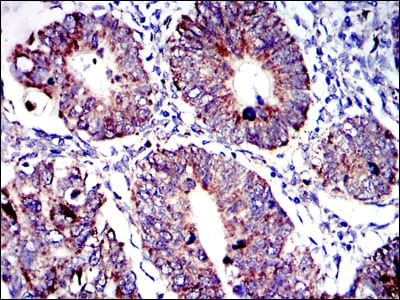

- Immunohistochemical analysis of paraffin-embedded human rectum cancer tissues using AIF mouse mAb with DAB staining.